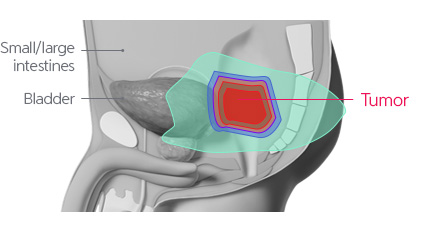

Due to functional and cosmetic reasons, surgical operations may be restrictive. Although high dose radiotherapy is implemented, the level of radiation transferred is limited. Therefore, it is difficult to implement high dose therapy with the X-ray treatments and side effects are common.

For recurrent rectal cancer that has been previously treated with radiotherapy, it is known that tumor removal is difficult and that there are limitations in the cosmetic and functional aspects when treated with surgical operations. Therefore, there are many cases where high dose radiotherapy is implemented. In such cases, even if treated through intensity modulated radiotherapy, side effects from radiation exposure to the surrounding normal organs are common, and for 5 years, the tumor control rate has been less than 50%. However, proton treatment is expected to decrease the level of radiation exposed to the surrounding normal tissues while transferring a high dose of radiation to the tumor for effective removal.